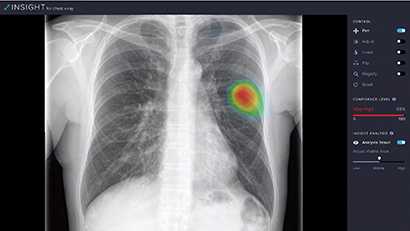

Medizinische Bildgebung

KI-gestützte Tools können ein zusätzliches "Augenpaar" sein, das Klinikern hilft, Bilder schnell zu lesen, Messungen zu berechnen, Veränderungen zu überwachen und dringende Befunde zu identifizieren, um Arbeitsabläufe zu optimieren und die Patientenversorgung zu verbessern.

Die Edge Solutions von NVIDIA sind darauf ausgelegt, kontinuierliche Datenströme am Netzwerkanrand zu erfassen und zu berechnen. Mit fortschrittlicher Bild-, Video-und Signalverarbeitung können in der Ki eingebettete medizinische Instrumente Chirurgen bei der Ausführung von weniger invasiven, gezielteren Operationen, Radiologen bei der Ermittlung von Diagnosen und Sonographen bei der Ausführung schneller und präziser Echokardiogramme schützen. Mit der NVIDIA EGX Platform können Sie das Gesundheitswesen auf den neuesten Stand bringen.

Ki hilft Stammespatienten mit "Kovid 19"-Symptomen

Das Startup LUnit von Ki und die von der CE-Kennzeichnung gekennzeichnete Lösung, LUnit Insight CXR, erkennen mithilfe von Ki 10 verschiedene Radiologische Befunde auf Röntgenstrahlen in der Brust, einschließlich einer Lungenentzündung, die häufig bei Patienten mit CVivid und in Sekundenschnelle in potenziell krebserregenden Lungenknollen vorkommen, schnell.